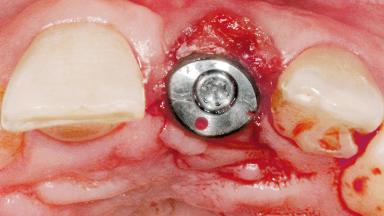

A 39-year-old male patient presented with a chief complaint of discomfort and gingival discoloration around his maxillary left central incisor. He was in good general health and was a non-smoker. His past dental history was significant because of the traumatic fracture of tooth 21 in a sporting accident at age 13. Initial dental treatment included endodontic therapy and a full-coverage restoration. The patient became symptomatic 5 years later, when structural failure of the tooth resulted in the dislodgment of the crown. Endodontic retreatment, apical surgery, and post-and-core restoration were performed.